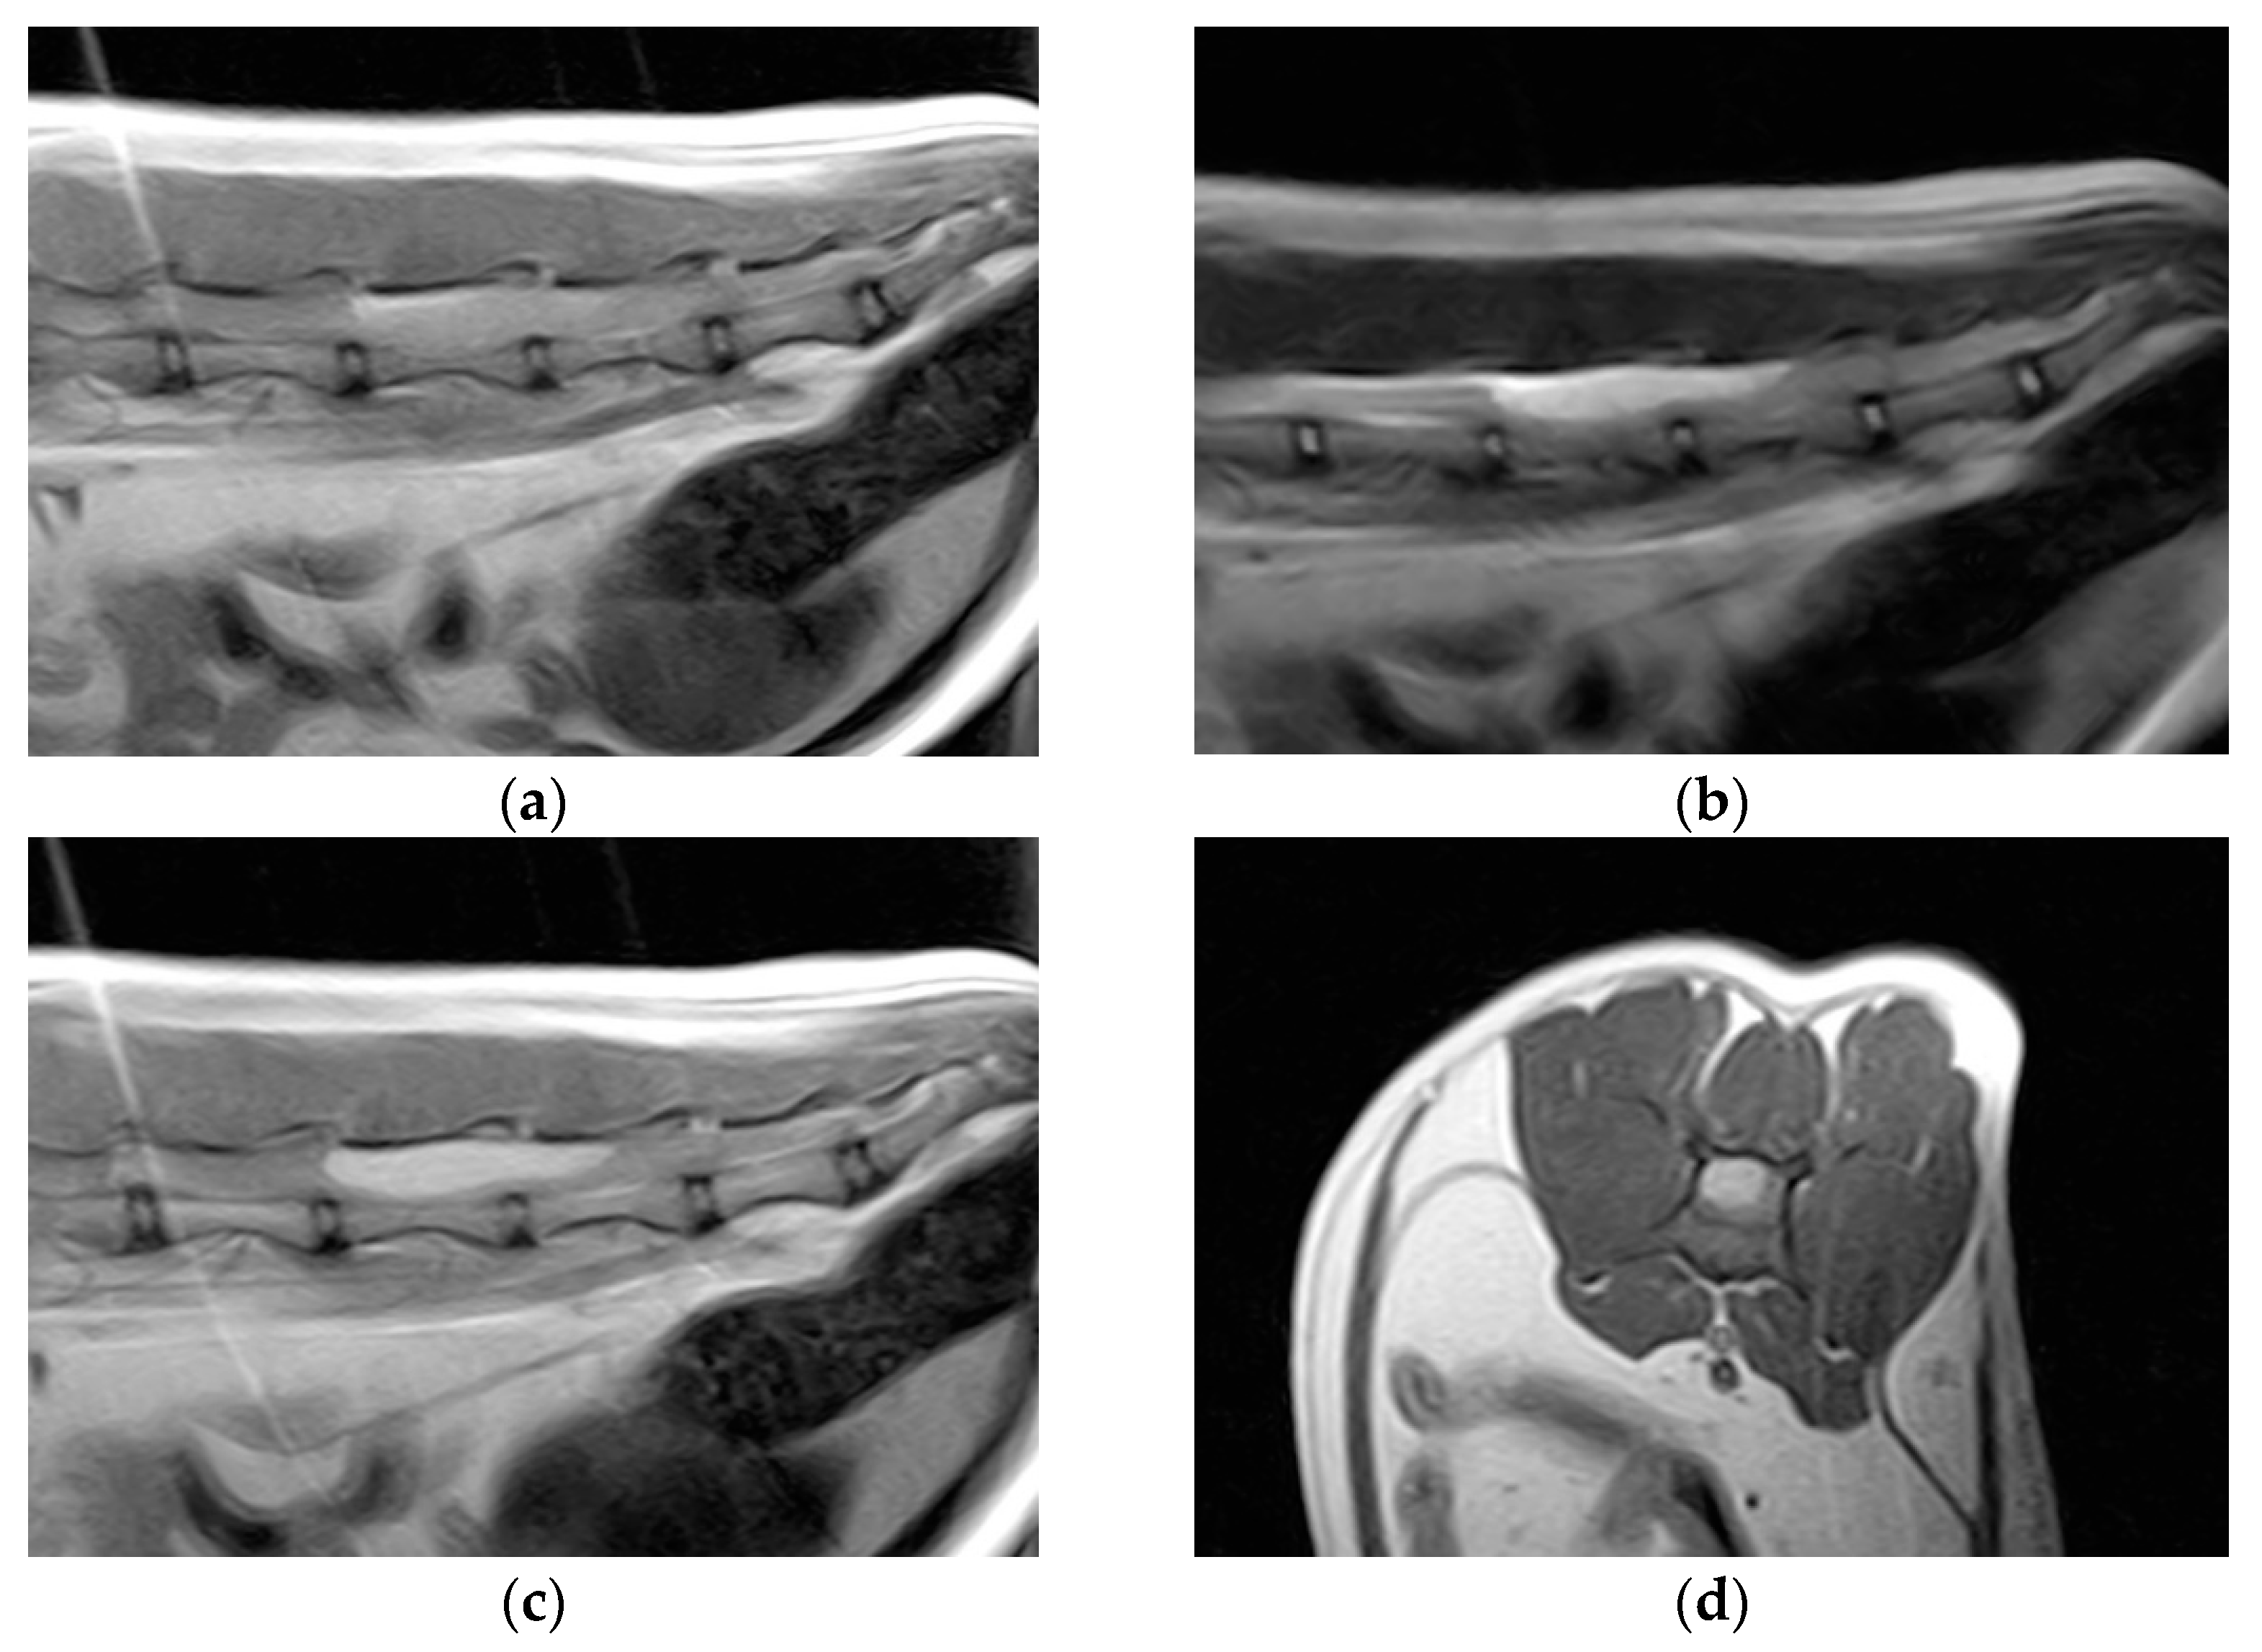

Hematology and blood biochemistry were unremarkable. Thoracolumbar column radiographs were normal. The cat was anesthetized and positioned for magnetic resonance imaging (MRI) of the thoracolumbar spinal cord (Esaote Vet-MR 0.2T, Genoa, Italy). T1-weighted sagittal and transverse scans, T2-weighted sagittal and transverse scans, and T1-weighted sagittal and transverse scans post-contrast (0.1 millimoles/kg of gadoteric acid—Claryciclic®, GE Healthcare s.r.l., Milano, Italy) were acquired. MRI identified an intradural extramedullary space-occupying mass extending from L5 to L6. The mass was dorsal and elliptical in shape (35 mm length, 8.3 mm width, and 7.2 mm height) and had sharp margins. It was homogeneously hyperintense in T2-weighted and isointense in T1-weighted scans and exhibited marked and homogeneous contrast enhancement in the T1-weighted post-contrast scans. The mass caused severe spinal cord compression (Figure 1).

Figure 1.

Magnetic resonance imaging of the spinal cord of the cat. (a) Preoperative sagittal T1-weighted image showing an isointense lesion on the dorsal side of the thoracolumbar spinal cord extending from L5 to L6. (b) The lesion is hyperintense on the T2-weighted images. (c) Marked lesion enhancement visualized on contrast-enhanced sagittal T1-weighted images. (d) Contrast-enhanced transverse T1-weighted image.

In human medicine, the radiological features of MEPL are not specific; studies have shown isointensity or hypointensity in T1-weighted imaging and hyperintensity in T2-weighted imaging with T1-weighted imaging showing marked enhancement after the use of contrast agents [23,24,28]. Those findings are consistent with the results in our case and those of the reported case of feline PNET, although other intradural tumors, such as meningioma, nerve sheath tumor, lymphoma, and metastasis, show the same radiological pattern [35].